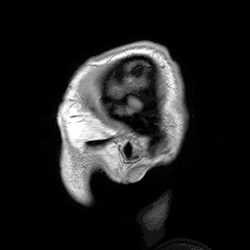

A ressonância magnética (MRI) usa campos magnéticos e ondas de rádio para produzir imagens de duas ou três dimensões de estruturas cerebrais de alta qualidade sem uso de radiação ionizante (raios-X) ou traçadores radioativos.